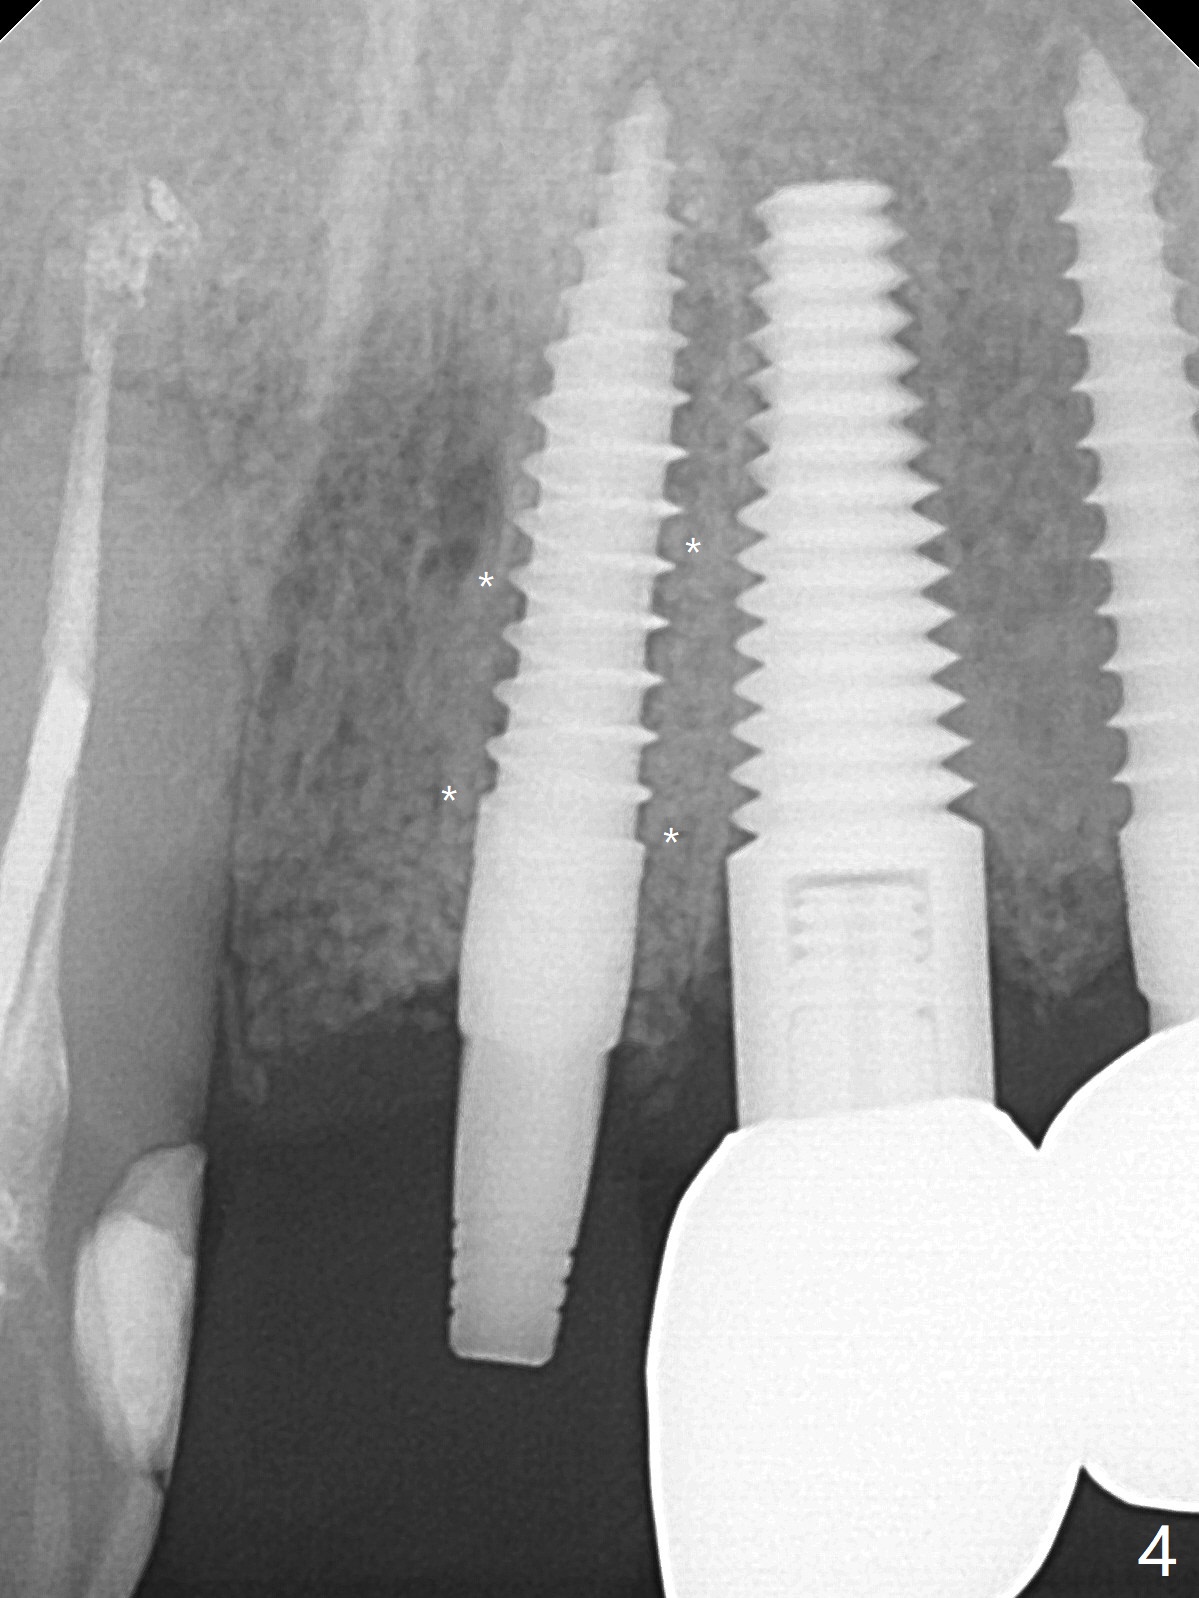

徒手种植不准确,需要反复调整,例如,为了避免接近侧切牙植体,中切牙钻洞开始于牙槽窝腭侧骨壁近中,结果接近切牙管(图一:红虚线),然后使用Lindamann bur移动钻洞,结果又太接近侧切牙(图二)。最后使用2毫米钻头试图改变钻洞方向,结果基台太接近侧切牙牙冠(图三)。而导板植入快,利索。 植入皮质骨骨粉(图四:*)后,制作临时牙冠。大约术后11天临时牙冠脱落(可能基台太短),病人没有及时复位,4天后牙槽窝愈合,可能变小,牙冠就位有些困难,造成颊侧牙龈发白(图五)。一周后牙冠又脱落,衬里后(图六:*)颊侧牙龈又显得饱满。